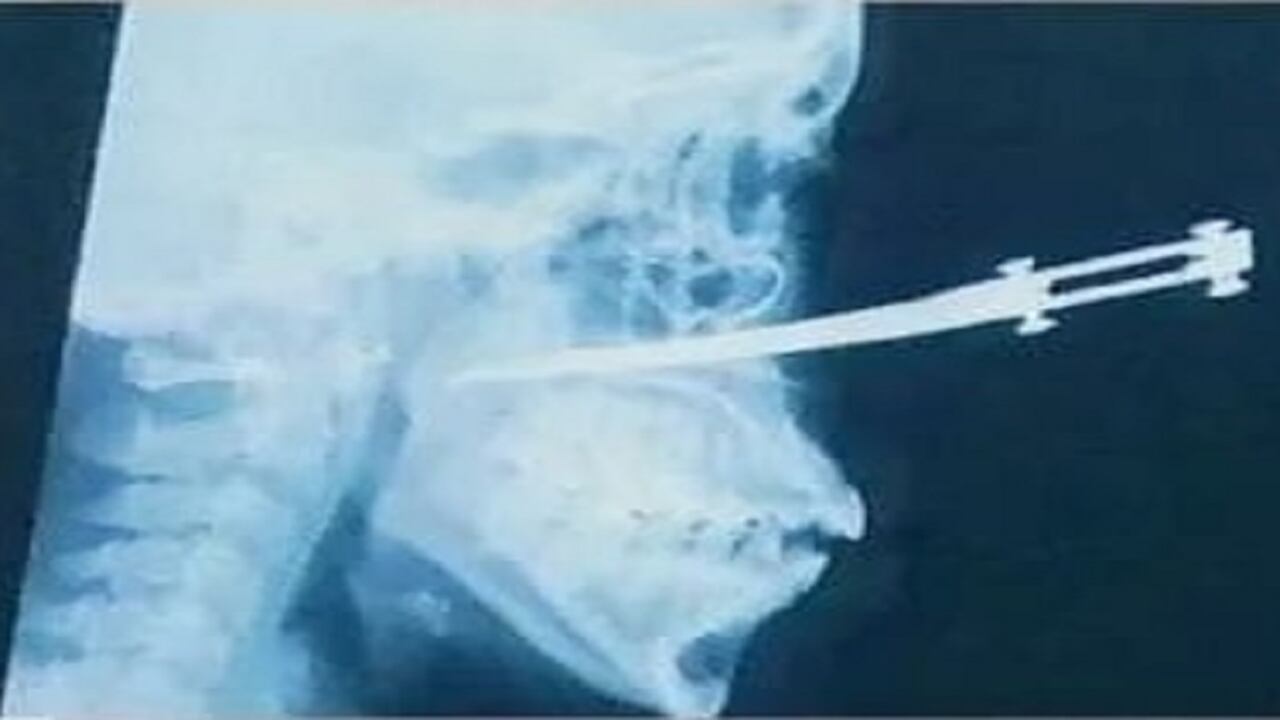

Después de delicada cirugía extraen cuchillo del rostro de mujer herida en atraco

Yoleidis Montalbán fue atacada cuando se dirigía a su trabajo, en el sector de El Pozón, en Cartagena.